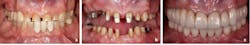

The decision as to which type of glass ceramic restoration (complete or partial coverage) considered the extent of damage, presence of fracture lines, and resistance and retention form.6,7

For partial coverage restorations, defect-specific tooth preparations removed all the caries and created proper retention form. Inlay or onlay partial coverage preparation design was then chosen based on the remaining tooth structure.1 The complete coverage restorations were approximately 1.2 mm in depth, and marginal finishing burs were employed.